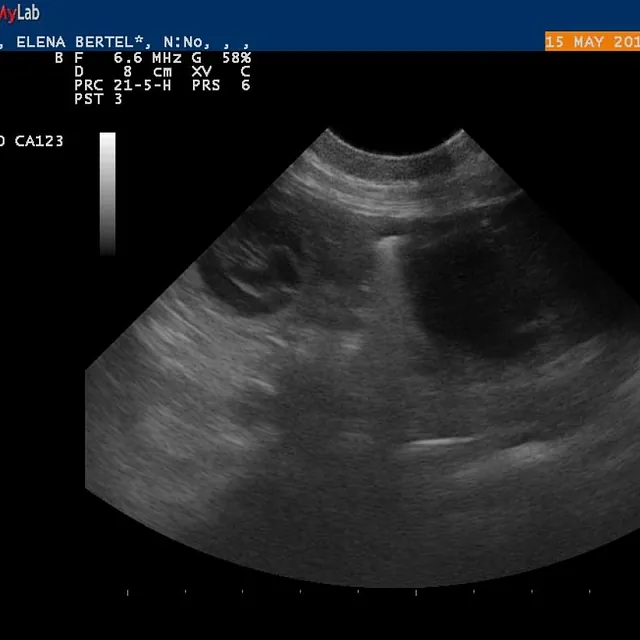

15.05.2017

Alice er drægtig!

e-kuld, 2017, sommer, kennel basta dog, schnauzere, schnauzerhvalpe, schnauzeropdræt, mellemschnauzer, alenzo, alice, hvalpe, købe schnauzer

Dejlig, dejlig nyhed!!!

Alice (Allegra)  er drægtig!

Scanning i dag har nemlig bekræftet den dejlige nyhed!

Hvor mange hvalpe er der inde? Tja, en del af dem kan du se på de billeder fra scanning :)

Nu krydser vi fingre for at alt går godt og vi får dejlige hvalpe efter de smukke og dygtige forældre!

P.S. Scaninngsbillederne ved klik på dem vil kunne ses i større størelse!